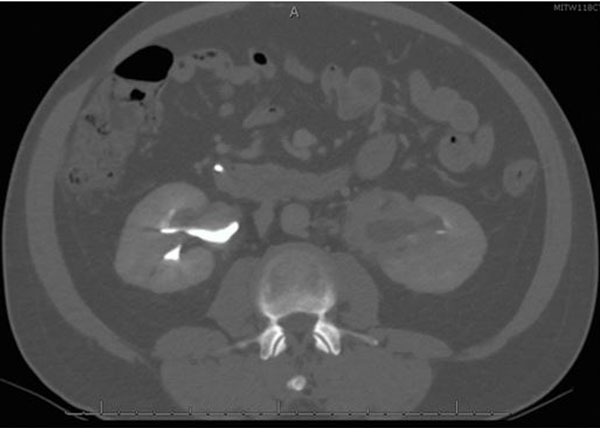

He was discharged from the hospital and seen in surgery clinic, where a bile duct resection, left liver lobe resection, and Roux-en-Y hepaticojejunostomy for possible cholangiocarcinoma were recommended. At this point, he reported that his initial symptoms had improved since his ERCP. His physical exam was normal and his liver chemistry tests revealed mild transaminitis. Total protein and albumin were normal. A computed tomography (CT) abdomen with contrast demonstrated a mass-like thickening of the CHD wall near the right and left hepatic duct bifurcation measuring 13 mm by 17 mm (Figure 2). He also had bilateral hydronephrosis, worse on the right, with abnormal mass-like thickening of the urothelia and retroperitoneal fibrosis on the CT (Figure 3). Given this finding, the differential diagnosis included consideration of IgG4 cholangiopathy, however measured IgG4 was normal at 42.4 mg/dL. A week later, he underwent another ERCP for continued imaging abnormalities and to reobtain tissue to rule out malignancy, which showed mild but improved structuring from the CHD to the hilum and redemonstrated the hilar mass. Samples of the mass for cytology and fluorescence in situ hybridization (FISH) were taken, and the stents were replaced.

Figure 3: CT image showing left greater than right urothelial thickening, with associated mild left hydronephrosis. CT: computed tomography.